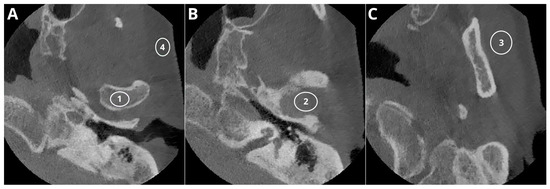

- Mandibular condyle.

- TMJ articular space.

- Masseter muscle.

- Buccal adipose tissue.